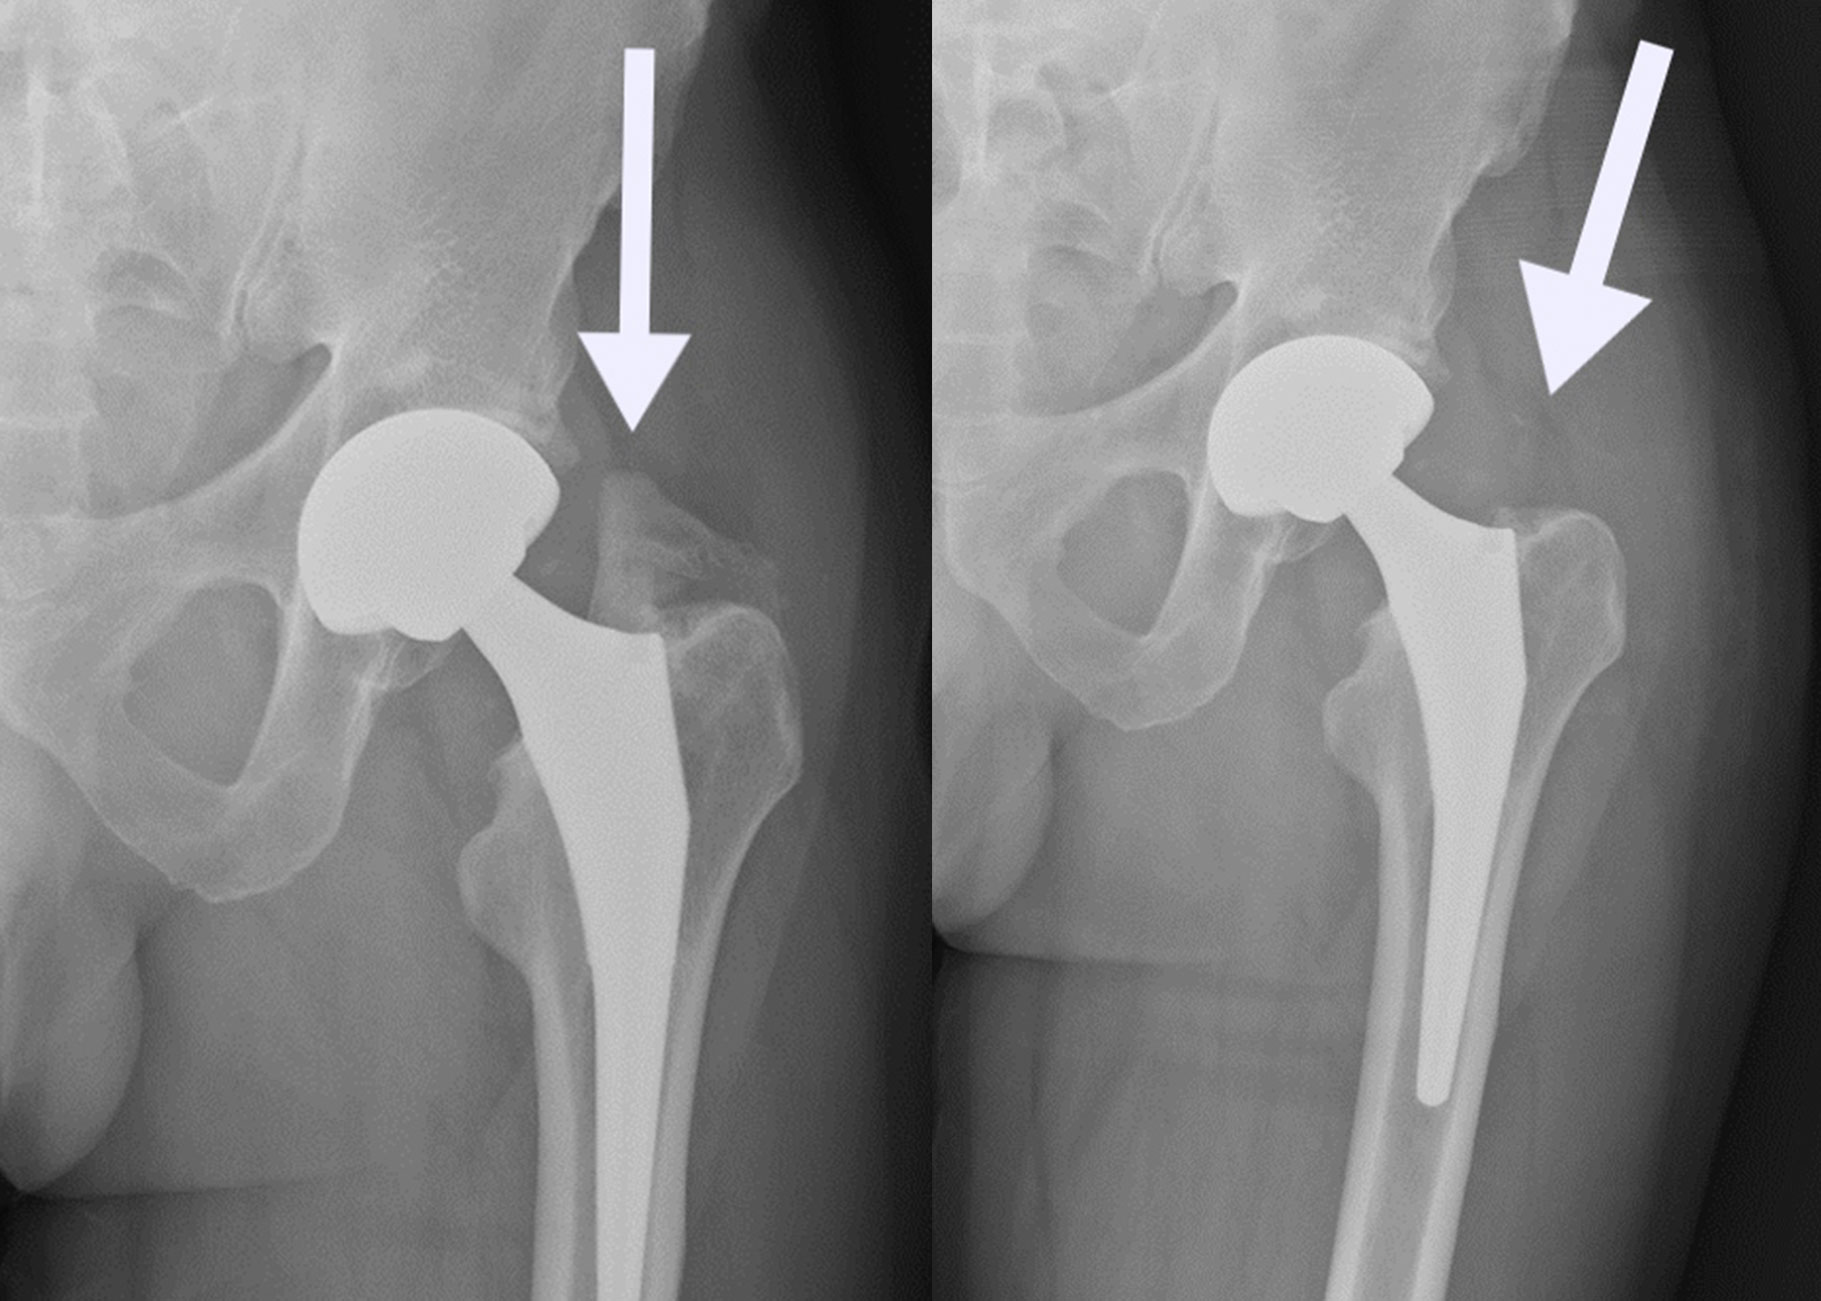

(Left)  In this image, HO has developed after hip replacement. (Right) This image shows the hip after surgery to remove the HO.

HO after hip replacement should be removed after it has fully matured, which may take up to 3 years from the initial hip replacement.

Recovery from surgery depends on where your HO is located and how big it is. Preventive treatment is often used after HO removal to keep it from coming back. Depending on where the HO is, you may have muscle weakness, continued pain, or a limp after surgery.